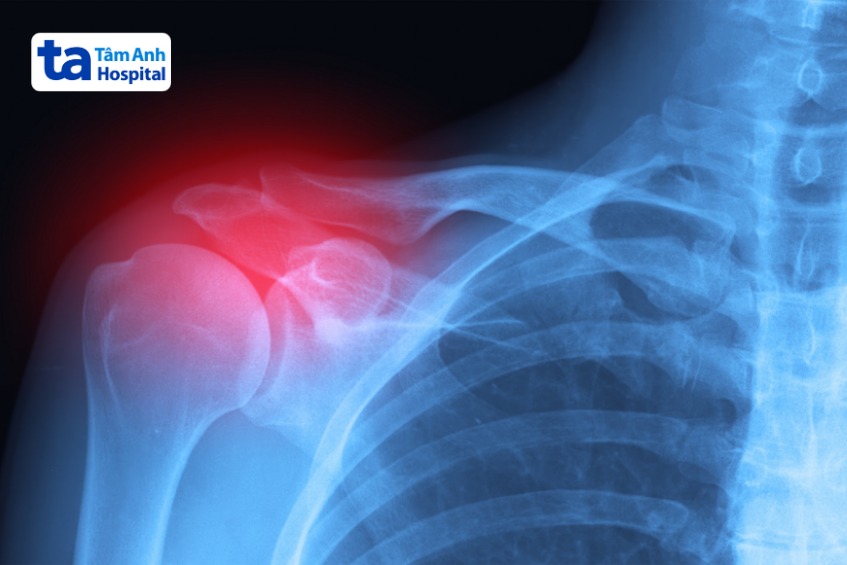

Chụp X-quang: Thường được sử dụng để chẩn đoán nhiều loại bệnh lý, có thể giúp phát hiện các khối u hoặc tổn thương bất thường trên xương, góp phần chẩn đoán ung thư xương. Ngoài ra, chụp X-quang còn được sử dụng để kiểm tra các dấu hiệu của viêm khớp, chẳng hạn như hẹp khe khớp, mọc gai xương, gãy xương… hay sự thay đổi cấu trúc của khớp, sự liên kết và vị trí của các khớp sau phẫu thuật hoặc điều trị.